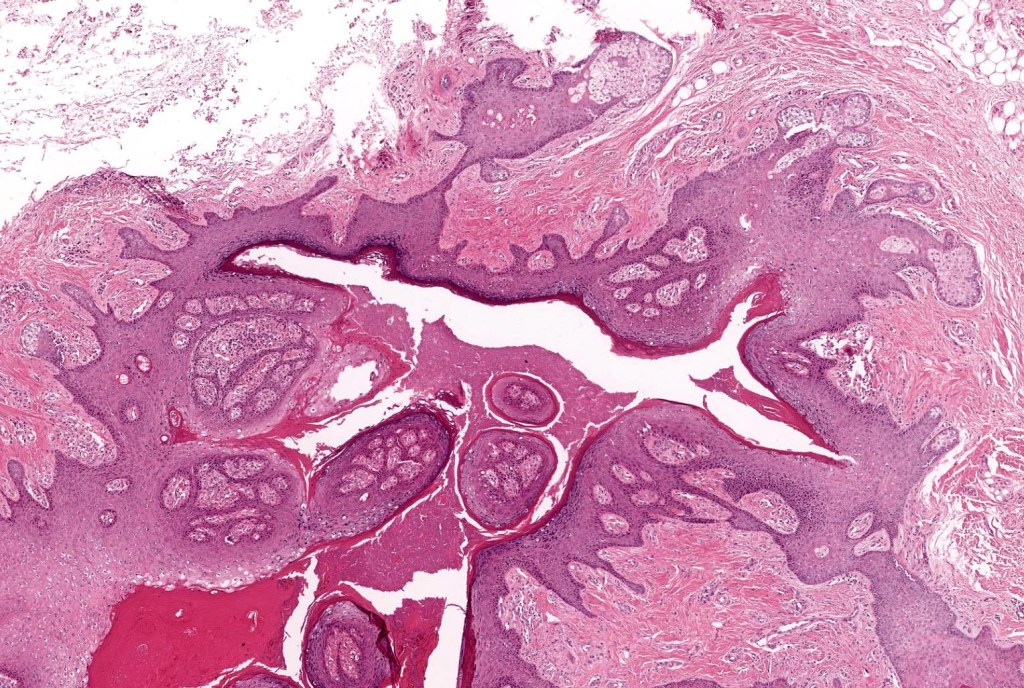

•Circumscribed dermal nodule with a characteristic silhouette

•An infundibular cyst is surrounded by laminated dermal collagen, elastic fibers, blood vessels, adipocytes & spindle cells separated from the adjacent dermis by a retraction artifact

•The cyst contains keratinous debris, and its wall shows conspicuous sebaceous & sometimes hair follicular elements are also evident